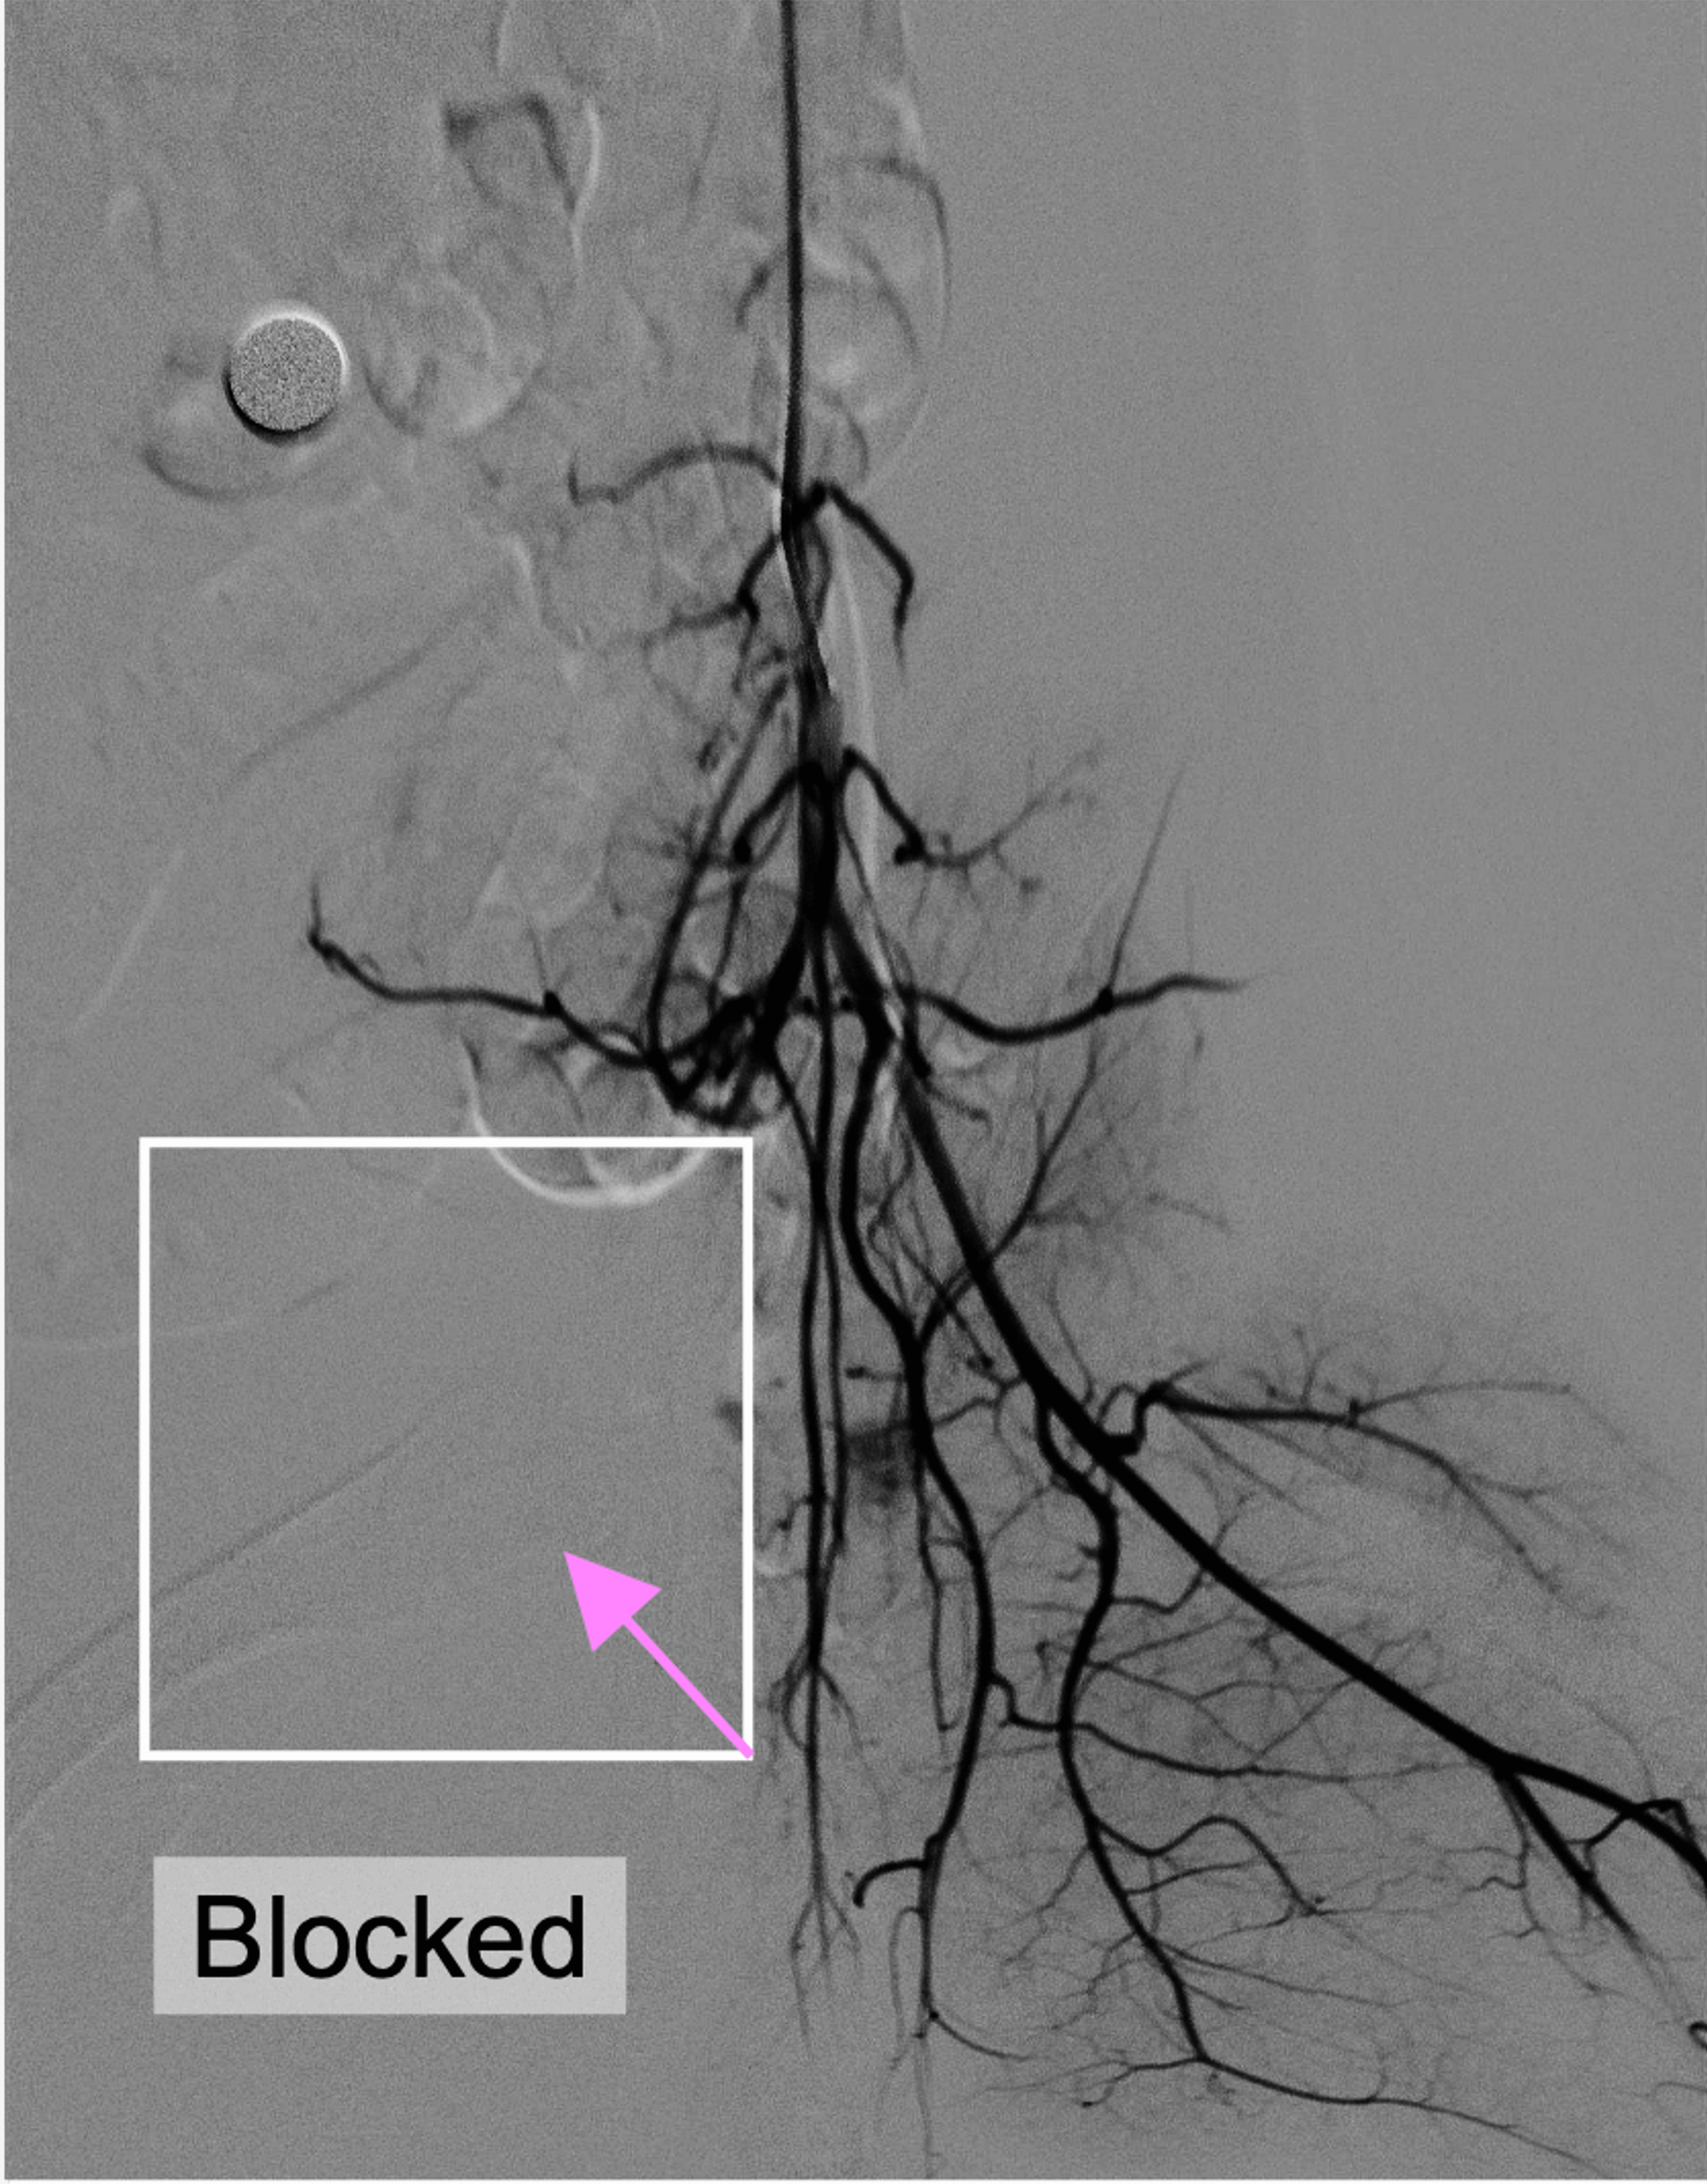

1 out of 2 heart attack patients still develops microvascular obstruction (MVO), blockage in the heart’s smallest blood vessels — even after timely treatment. MVO remains a major driver of poor recovery, heart failure, and long-term mortality after heart attack treatment.

SonoRobotics develops catheter-based ultrasound technology for thrombus disruption and microvascular protection in PCI workflows.